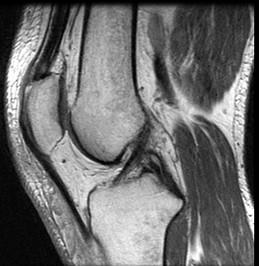

问题 男,39岁,右膝关节有外伤史,感膝关节疼痛,活动后加剧,请结合所提供的图像,选择最佳选项 ( )

选项 A、胫骨骨折 B、后十字韧带撕裂 C、前十字韧带撕裂 D、内侧半月板撕裂 E、未见异常

答案 B